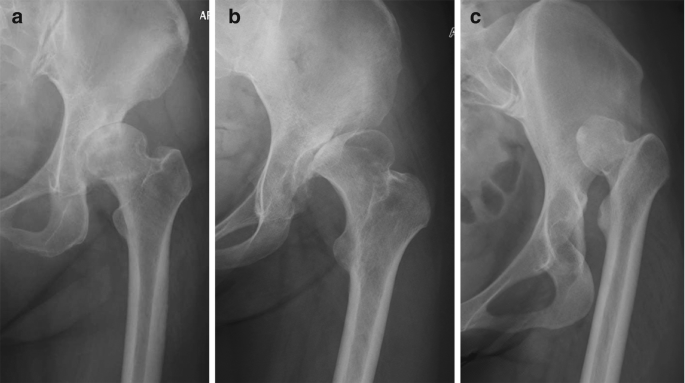

(2) 第二种分型,Hartofilakidis分型,

随后,1996年,希腊学者Hartofilakidis提出另一套髋臼发育不良分型标准:

髋臼发育不良Hartofilakidis分型

I级是发育不良,其中股骨头包含在原来的真髋臼内。

2级是低位脱位,股骨头与假髋关节相连,假髋臼的下缘与真髋臼的上缘接触或重叠,呈现两个重叠的髋臼外观。

3级是高位脱位,股骨头向后方移位,真假髋臼无接触。